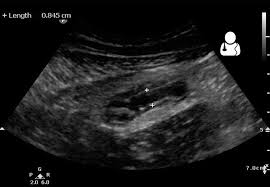

X-ray is a method of detecting a disease during health treatment. But various things should be taken care of while doing X-ray. During pregnancy, it is better not to take X-rays as much as possible. Because it can negatively affect the fetus inside the womb.

X-ray is a ray (ray), which helps to detect diseases in the body and also causes some damage to the body. X-rays emit radiation that deactivates and kills cells in the body. Similarly, due to the radiation of high light emitted from X-ray during pregnancy, there may be problems in the growth and development of the fetus inside the womb, due to which it may cause birth defects, slow growth and development of the baby after birth and may even increase the risk of miscarriage.

There are three trimesters of pregnancy - first, second and third. X-rays during pregnancy can have a negative impact on the first trimester. At this time, as the fetus is developing inside the womb, the main organs and systems of the fetus are being formed. X-rays in such a situation can cause problems in the development of the fetus due to the radiation emitted from it. Because the radiation coming out of the X-ray deactivates and kills the cells that are developing inside the embryo.

Affecting the division of that cell, it also harms the divided cell. This affects the physical and mental growth of the fetus. Congenital disability, delayed growth and development after birth can be a problem. Slow speech, slow walking may also happen.

There is sometimes a risk of miscarriage due to X-ray, which is more in the first trimester of pregnancy, while the risk of miscarriage is comparatively less in the second and third trimester of pregnancy. Likewise, fetal growth may be developing in the second and third trimesters. At this time, the risk in these trimesters is lower than in the first trimester, but due to X-ray radiation, the fetus inside the womb may be at risk of serious diseases such as cancer.

But saying this does not mean that X-rays will affect the fetus inside the womb. It varies according to the health of the pregnant woman and the amount of X-rays. Also, the risk of radiation varies from person to person. The more x-rays done, the greater the risk.

X-rays near the abdomen and uterus pose an even greater risk. X-ray radiation can directly affect the fetus inside the womb, while it affects the limbs less.